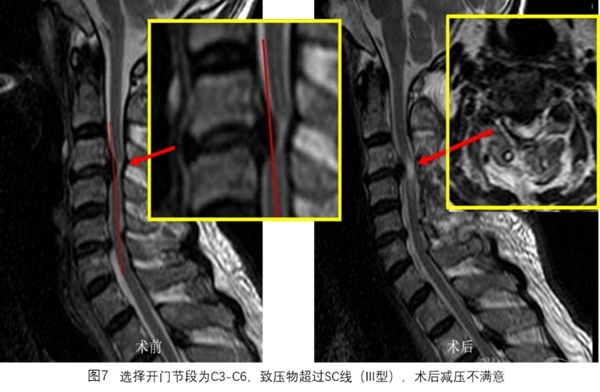

SC线同时反映颈椎管曲度、脊髓曲度与致压物的关系,根据SC线及其分型能更好地预测颈椎开门椎管成形术后脊髓减压的效果(图3~图8)。

选择开门节段后,划出SC线,分型为I型开门术后减压满意,II型大部分可获得减压,III型减压不满意。